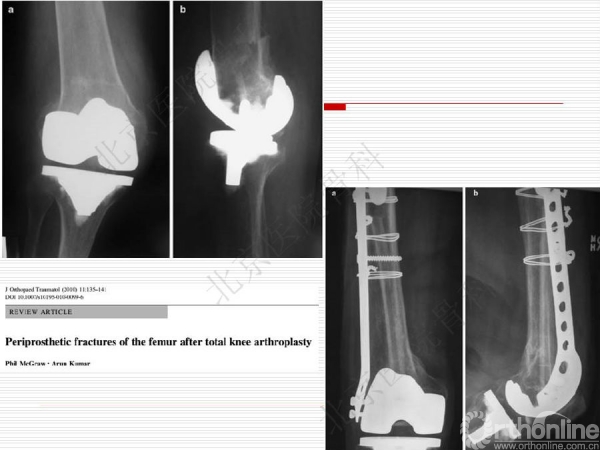

膝关节假体周围骨质疏松骨折1例

骨质疏松性骨折与创伤性骨折不同,是基于全身骨质疏松存在的一个局部骨组织病变,是骨强度下降的体现,也是骨质疏松症的最终结果。骨质疏松骨折是常见病、多发病,严重威胁中老年人身体健康,由此引起的骨质疏松性骨折,除了给患者本人造成极大的痛苦外,也给社会和家庭造成了沉重的经济和生活负担。来自北京医院骨科纪泉教授为我们带来一例经典的《膝关节假体周围骨质疏松骨折》病例,遂抗骨质疏松治疗预防再次骨折,任重而道远!